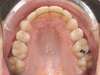

Cas 3 : Description

Encombrement aux deux arcades.Traitement par gouttières.

Avant

Après